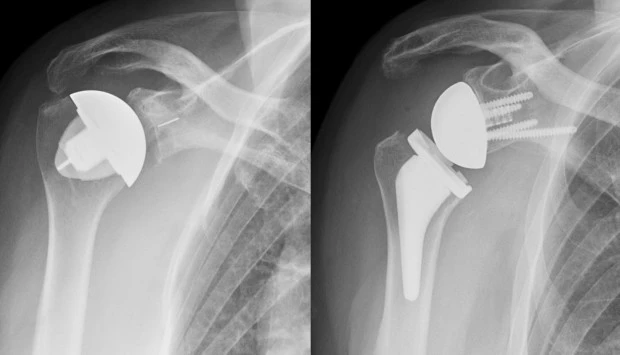

Μέχρι πρόσφατα ασθενείς με τέτοιες βλάβες ήταν αναγκασμένοι να υποστούν τις οδυνηρές συνέπειες της χρονιάς πάθησης ή του τραυματισμού τους. Ωστόσο, η ολική αρθροπλαστική του ώμου (ορθόδρομη και ανάστροφη) έχει πλέον καθιερωθεί ως μέθοδος θεραπείας με εντυπωσιακά αποτελέσματα. Σε αυτή την εγχείρηση αντικαθίστανται οι αρθρούμενες επιφάνειες των οστών του ώμου (κεφαλή βραχιονίου και ωμογλήνη ωμοπλάτης), ώστε να επανέλθει η λειτουργία του σχεδόν στο φυσιολογικό. Είναι μάλιστα μια εγχείρηση που έχει τεράστια αύξηση στον αριθμό ασθενών που υποβάλλονται σε αυτήν, κυρίως ασθενών με κατάγματα του ώμου, οι οποίοι σε άλλη περίπτωση θα έπρεπε απλώς να αφεθούν στην τύχη τους.

Όμως, η ολική αρθροπλαστική μπορεί να λύσει προβλήματα παθολογικών καταστάσεων και σε μεγάλες αρθρώσεις του άνω άκρου, όπως ο ώμος και ο αγκώνας. Ωστόσο, αυτό δεν έχει επικοινωνηθεί στο ευρύ κοινό των ασθενών μας και οι εγχειρήσεις αυτές μόλις τα τελευταία χρόνια αρχίζουν να αυξάνονται. Κι αυτό παρότι ολικές αρθροπλαστικές του ώμου και του αγκώνα πραγματοποιούνται εδώ και δεκαετίες με αποτελέσματα συγκρίσιμα σε επιτυχία με τις άλλες ολικές αρθροπλαστικές.